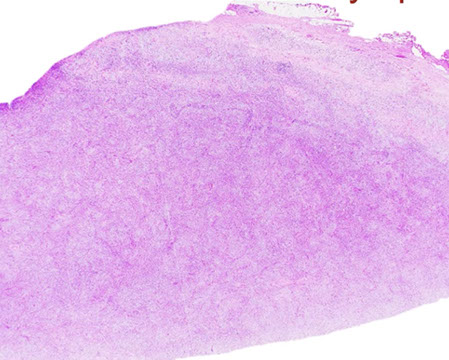

Micro: LN c diffuse nodal involvement showing pseudofollicular architecture (no true mantle zone) c large pale prolif centers c prolymphocytes (>11%; sm to med size cells c clumped chromatin and small nucleoli), paraimmunoblasts (larger, c round to oval nuclei, central red nucleoli)

CLL/SLL can have a perifollicular and/or follicular growth pattern

- can see prolif of small, mature lymphs c multiple prolif centers / pseudofollicles

CLL, proliferation centers (pseudofollicles), usually MUM1+